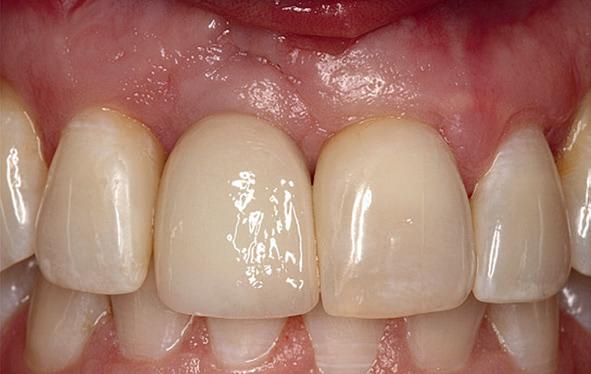

Implantologische behandelingen in het esthetische front vragen meer dan technische vaardigheid alleen. Ze vragen om overzicht, timing, vertrouwen en een team dat als vanzelf samenwerkt onder druk. Juist bij complexe casussen, waarin angst, infectie en hoge esthetische verwachtingen samenkomen, wordt zichtbaar hoe bepalend de rol van de tandartsassistent is.

Deze casus beschrijft een uitgebreide immediate implantaatbehandeling bij een patiënt die door meerdere collega’s werd geweigerd. Niet omdat de mogelijkheden ontbraken, maar omdat de complexiteit vroeg om een perfect afgestemde samenwerking. Het verhaal laat zien hoe de assistent in zo’n traject veel meer is dan een uitvoerende kracht of “mal”, maar een dynamische surgical guide die het proces mede stuurt, bewaakt en mogelijk maakt.De patiënt: wanneer alles samenkomt

De kern van haar vraag was eenvoudig en tegelijkertijd uitdagend: Is het mogelijk om mijn huidige brug te dupliceren en een nieuwe brug te vervaardigen met minder complicaties?